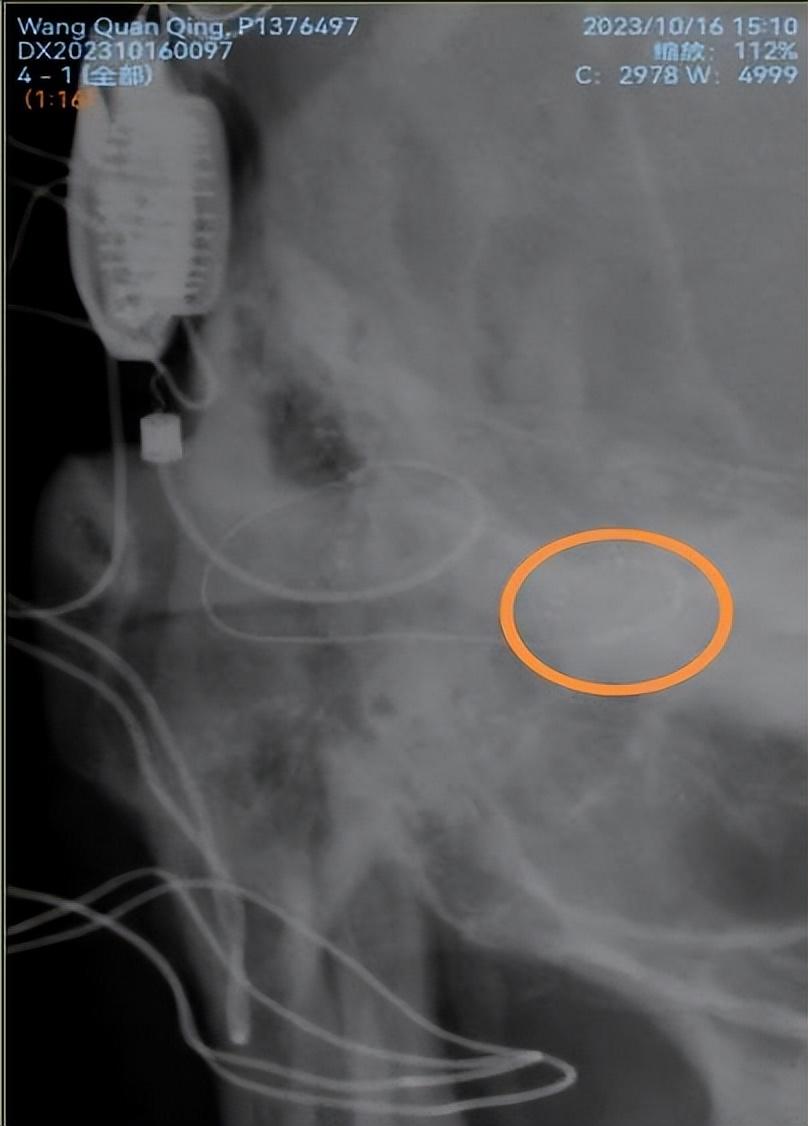

近日,南华大学附属第一医院耳鼻咽喉科同一天给两例患有双侧极重度感音神经性耳聋而佩戴助听器无效的患者开展人工耳蜗植入术,这也是衡阳市自主开展的第一例和第二例人工耳蜗植入术。此手术在科室主任江青山教授的指导下,由科室副主任陈祖尧博士主刀完成,手术顺利,术中电极阻抗测量以及神经反应测试皆为正常,术后第二天的头颅X片提示植入电极在耳蜗内布阵良好,表明手术取得了成功。患者需要做的就是等待一个月以后的开机调试和言语康复。

术后颅骨X片显示耳蜗植入电极位置正常